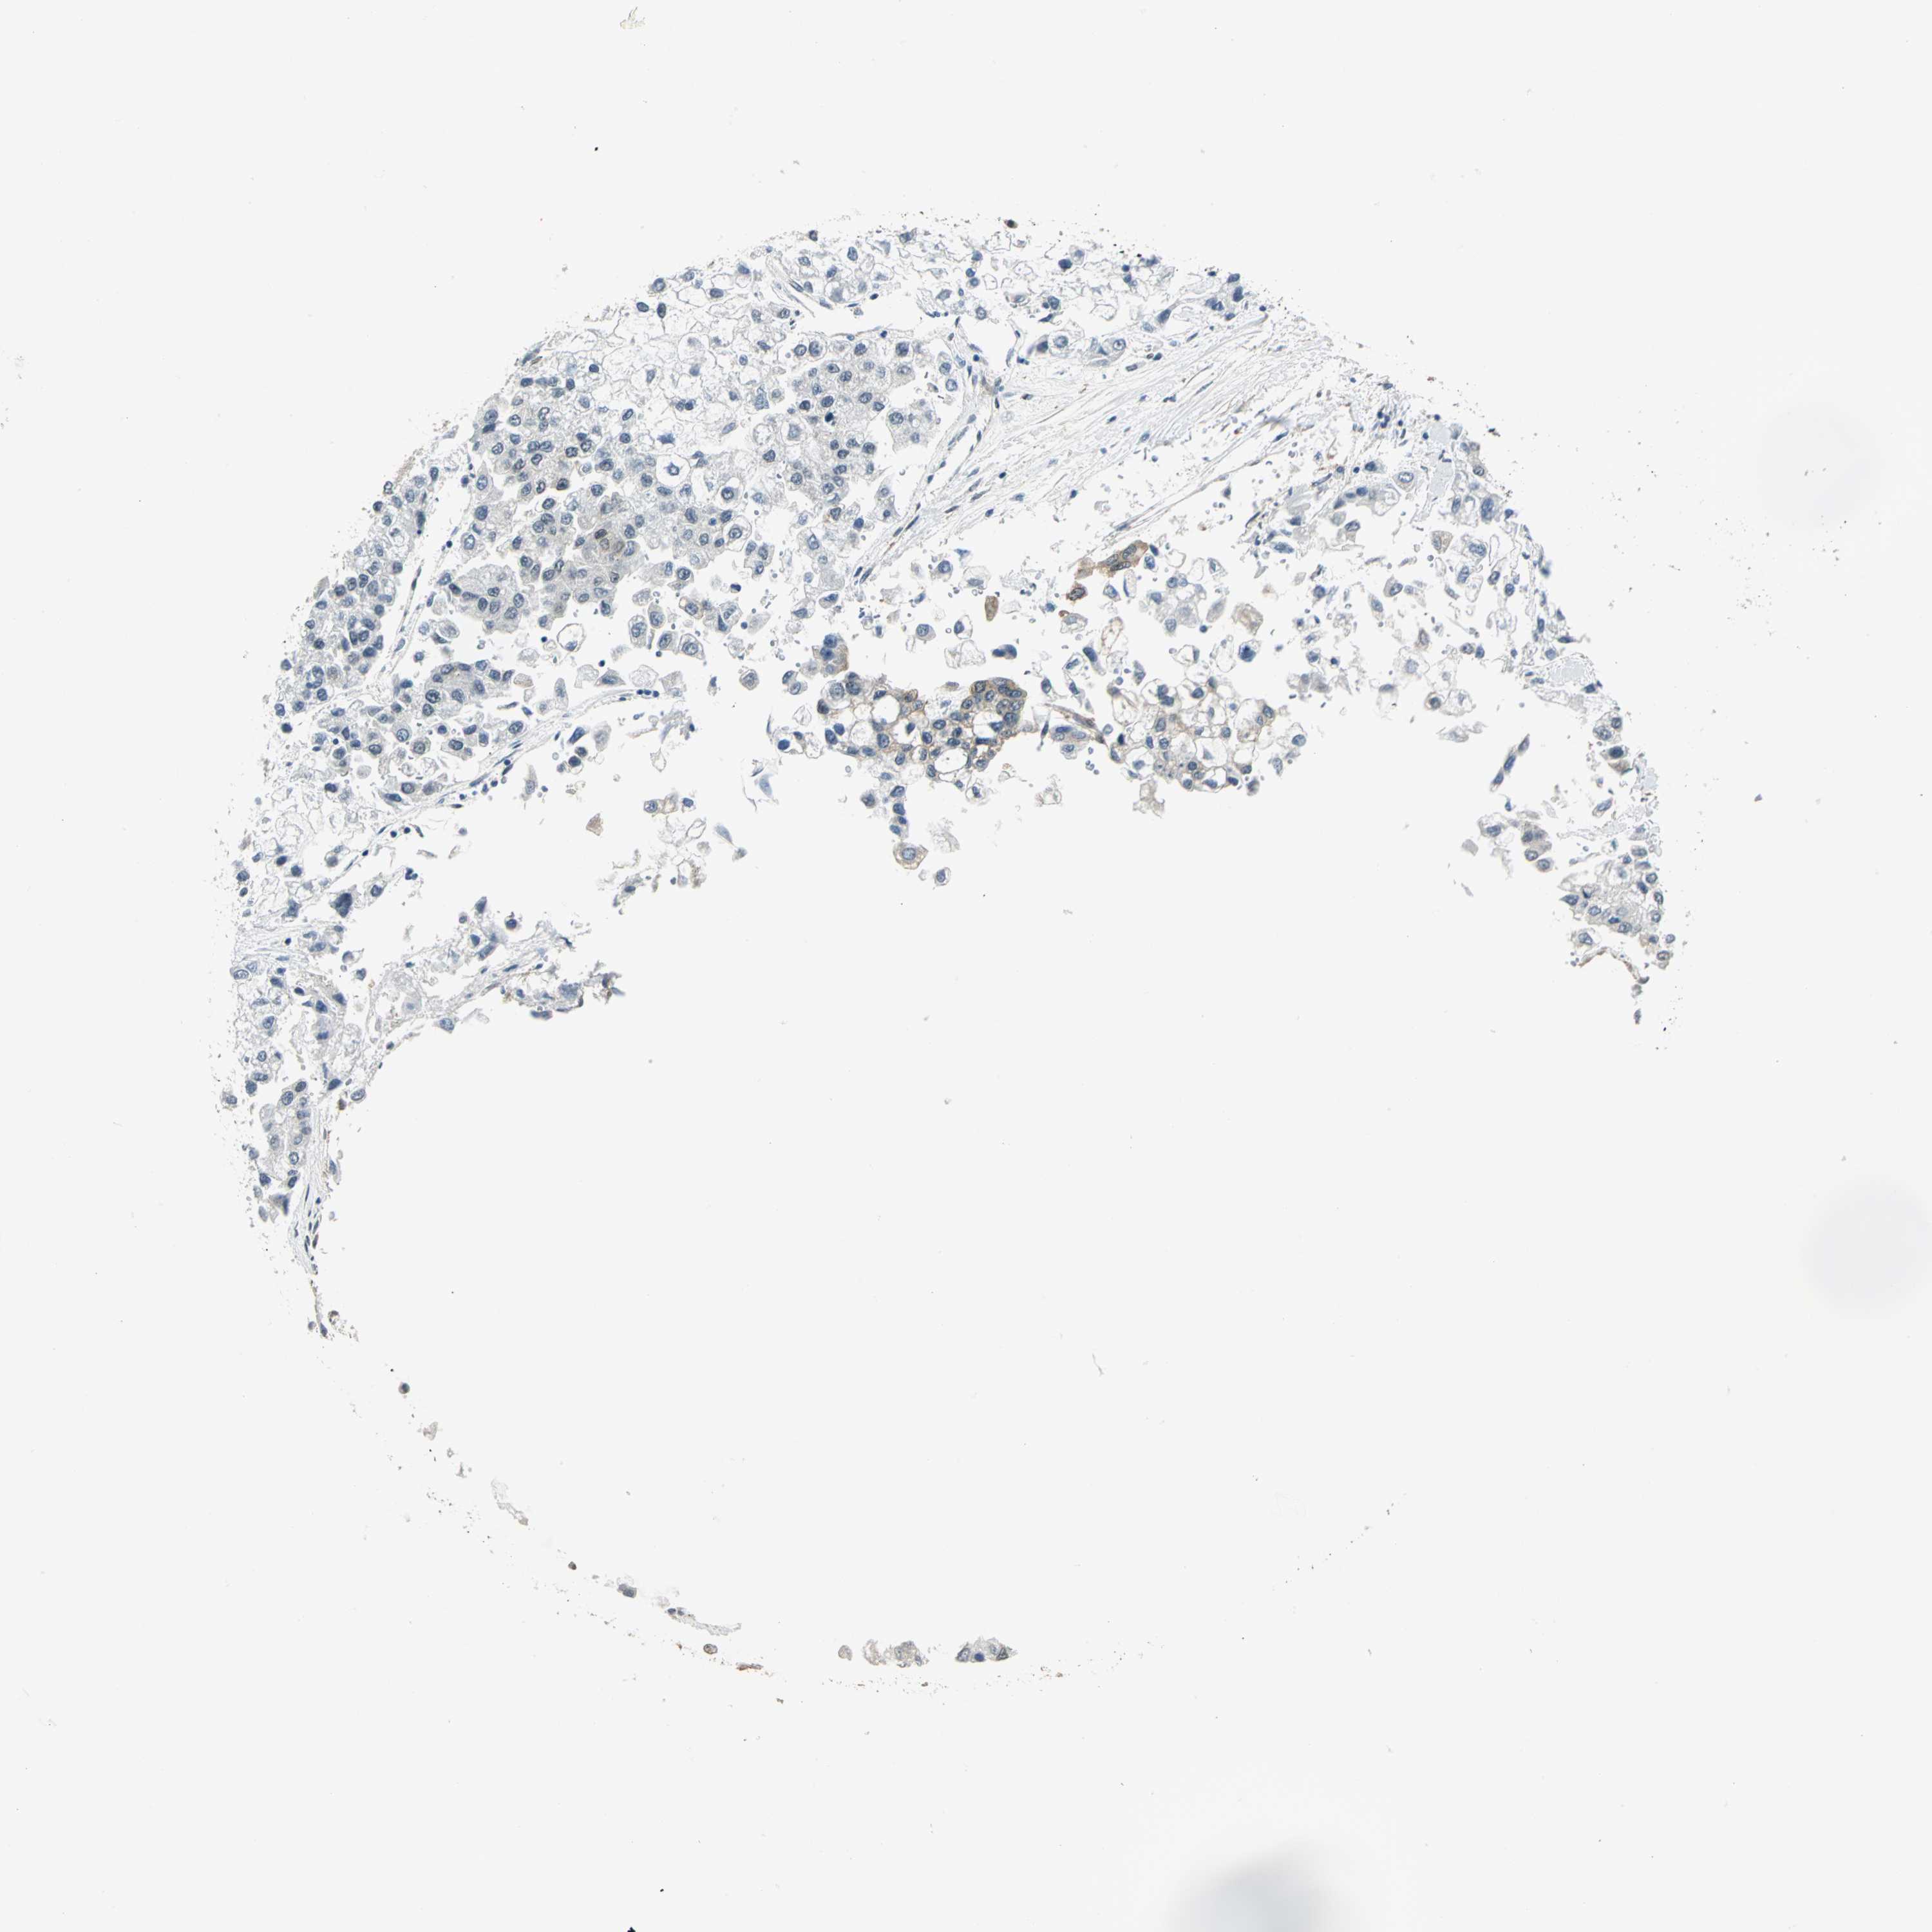

LIVER CANCER - Protein expressioni

A mouse-over function shows sample information and annotation data. Click on an image to view it in a full screen mode. Samples can be filtered based on level of antibody staining by selecting one or several of the following categories: high, medium, low and not detected. The assay and annotation is described here.

Note that samples used for immunohistochemistry by the Human Protein Atlas do not correspond to samples in the TCGA dataset.

Antibody stainingi

Antibody staining in the annotated cell types in the current human tissue is reported as not detected, low, medium, or high, based on conventional immunohistochemistry profiling in selected tissues. This score is based on the combination of the staining intensity and fraction of stained cells.

Each image is clickable and will lead to virtual microscopy that enables deeper exploration of all samples and also displays staining intensity scores, fraction scores and subcellular localization as well as patient and tissue information for each sample.

Antibody HPA020043

Antibody CAB005868

Staining

High

Medium

Low

Not detected

Intensity

Strong

Moderate

Weak

Negative

Quantity

>75%

75%-25%

<25%

None

Location

Nuclear

Cytoplasmic/membranous

Cytoplasmic/membranous,nuclear

Carcinoma, Hepatocellular, NOS

Cholangiocarcinoma